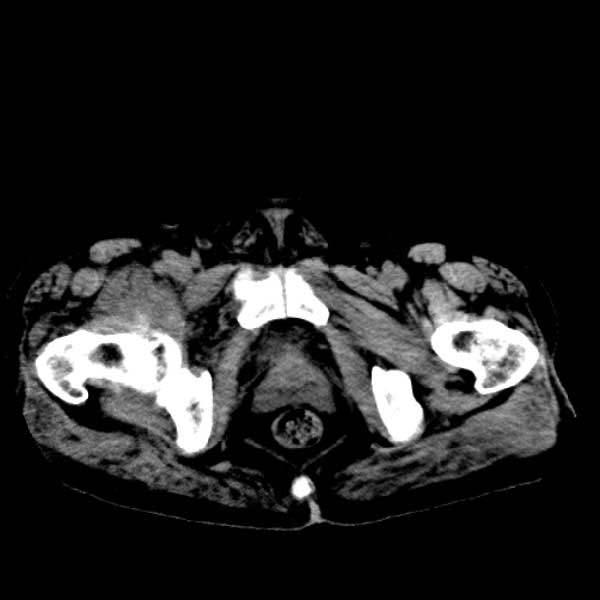

标题: CT13513:男 71 腹部疼痛20余天,近几天高热就诊,骨窗未见异 [打印本页]

标题: CT13513:男 71 腹部疼痛20余天,近几天高热就诊,骨窗未见异

考虑感染性病变可能性大,起源于阑尾?

感染,脓肿形成

考虑为化脓性阑尾炎.脓肿形成.及多肌肉累及.

考虑右侧腰大肌脓肿,向右髂窝、右腹股沟流注。

支持化脓性阑尾炎伴右髂窝脓肿、腰大肌腰方肌脓肿形成。

考虑腹腔及盆腔化脓性炎症,累及右侧髋关节及腹股沟区.

首先考虑化脓性阑尾炎伴腰大肌、腰方肌脓肿,不除外回盲部结核。

回盲部癌待排除。

患者肠镜检查考虑结肠癌,病理证实

患者肠镜检查考虑结肠癌,病理证实。肺部ct可见多发结节,考虑转移